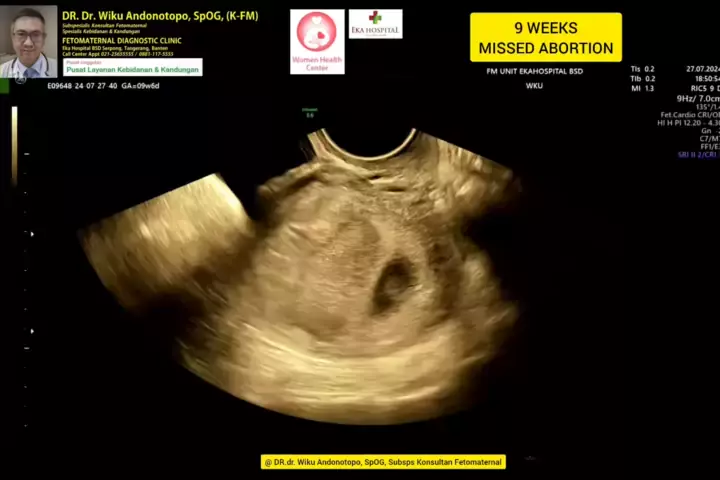

9 weeks Missed Abortion... #skriningkehamilan #drwikuandonotopo #drwiku_andonotopo #polikandunganekahospitalbsd #ekahospitalbsd #ekahospitalcibubur #ekahospitalpekanbaru #ekahospitalbekasi #rsiafamilypluit #grandfamilypik #usgkehamilansehat #usgkehamilan #usg4d #usg4dimensi #fetomaternal #usgfetomaternal #konsultanfetomaternal #fetomaternalpontianak #fetomaternalekahospitalbsd #fetomaternaljakarta #fetomaternalserpong #fetomaternaltangerang #fetomaternalmedan #fetomaternalpalembang #fetomaterna... More